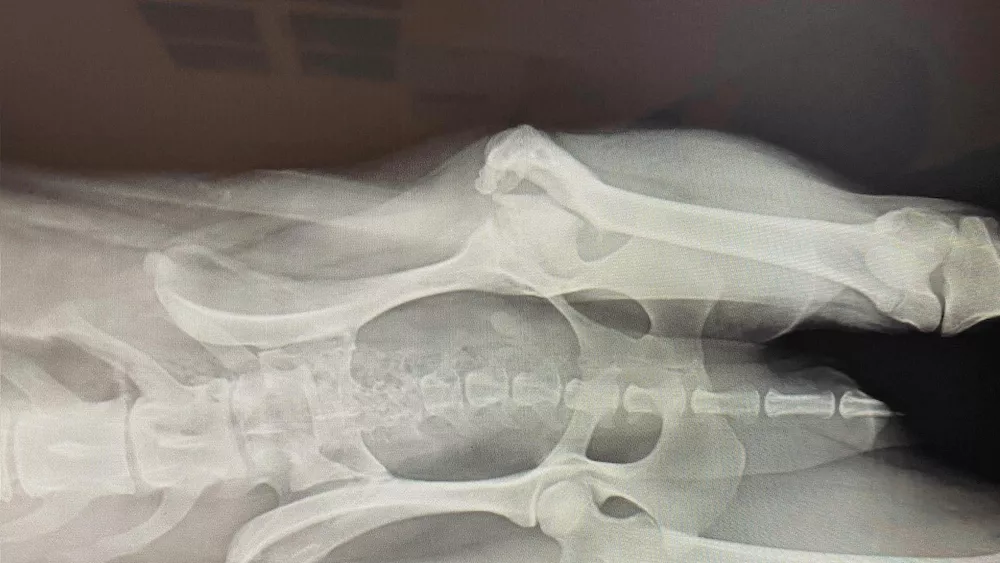

To get her the help that she needed, Tapatuk was surrendered by the community and we took her in at our Care and Rehabilitation Centre near Montreal, Québec. X-rays and further examination revealed that Tapatuk suffered from a major orthopaedic problem, among other things, and that she would require expensive treatments, including a surgery of several thousand dollars.